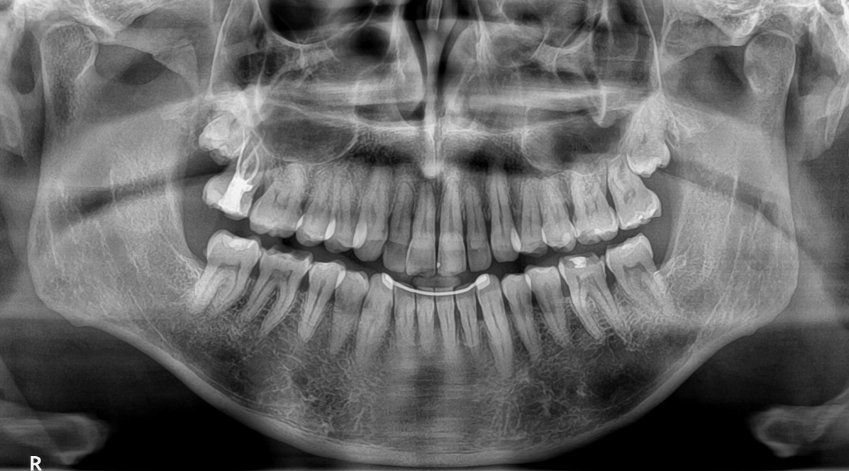

La técnica de la ortopantomografía se ha convertido en una de las pruebas diagnósticas más utilizadas por los higienistas en la actualidad. La prueba consiste en la realización de una radiografía panorámica dental donde se puede observar de forma nítida los dientes, el maxilar y la mandíbula cuidando la seguridad del paciente al utilizar una dosis baja de radiación.

Gracias a esta prueba los especialistas en salud bucodental podrán detectar caries, enfermedad periodontal causada por infecciones dentales, nivel de la estructura ósea, dientes pendientes de salir, cronología de los dientes en los niños para saber si es necesario iniciar un tratamiento o la apreciación de lesiones oseas patológicas como el estado del tabique nasal o los senos maxilares o la presencia de asimetrías.